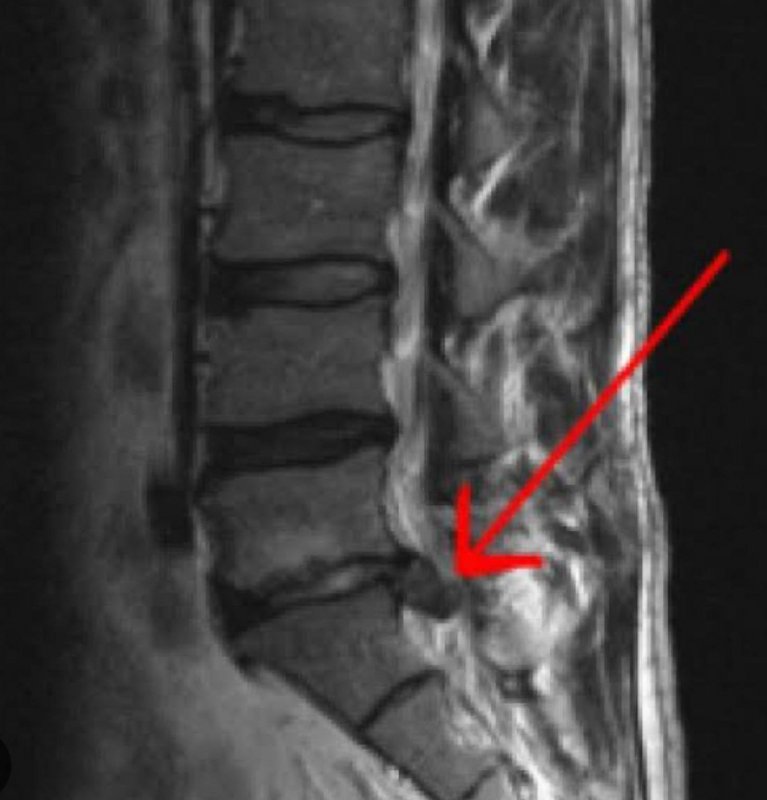

Hastalığın teşhisinin ilk olarak semptomların nasıl başladığının irdelenmesi ile başlayıp detaylı bir fizik muayene ve gelişmiş görüntüleme teknikleri olan MR ile rahatlıkla konulabileceğine işaret eden Cebesoy, “Bel fıtığının tedavisi şikâyetin ve fıtığın derecesine bağlı olmakla birlikte ilk olarak konservatif dediğimiz ameliyatsız yöntemlerdir. Bu yöntemler ilaç tedavisi ve fizik tedavileri içerir.